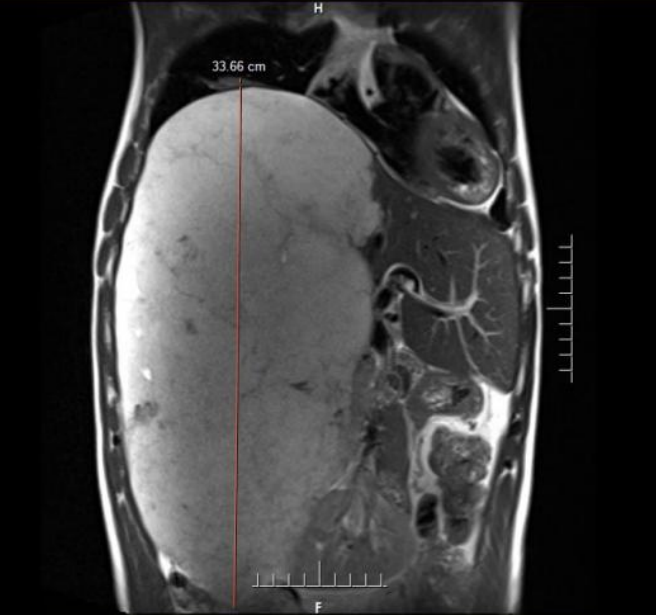

术前MRI提示肝脏巨大占位,纵向直径约34cm,直抵盆腔

近段时间,李先生因上腹持续不适前往中国科大附一院就诊。全面的影像学检查结果让他和家人震惊不已——腹腔里竟然长了一个巨大的占位性病灶,纵向直径约 34 厘米,从上腹一直延伸至盆腔,如同怀胎十月的胎儿般占据了腹腔大量空间,最终确诊为“肝脏巨大占位(肝血管瘤可能)”。

“如此巨大的肝血管瘤在临床上极为罕见,更危险的是它紧贴重要血管以及肝脏胆道等器官组织,甚至将右侧肾脏挤压到了左侧。”接诊的中国科大附一院副院长、普外科肝胆外科主任医师尹大龙介绍。